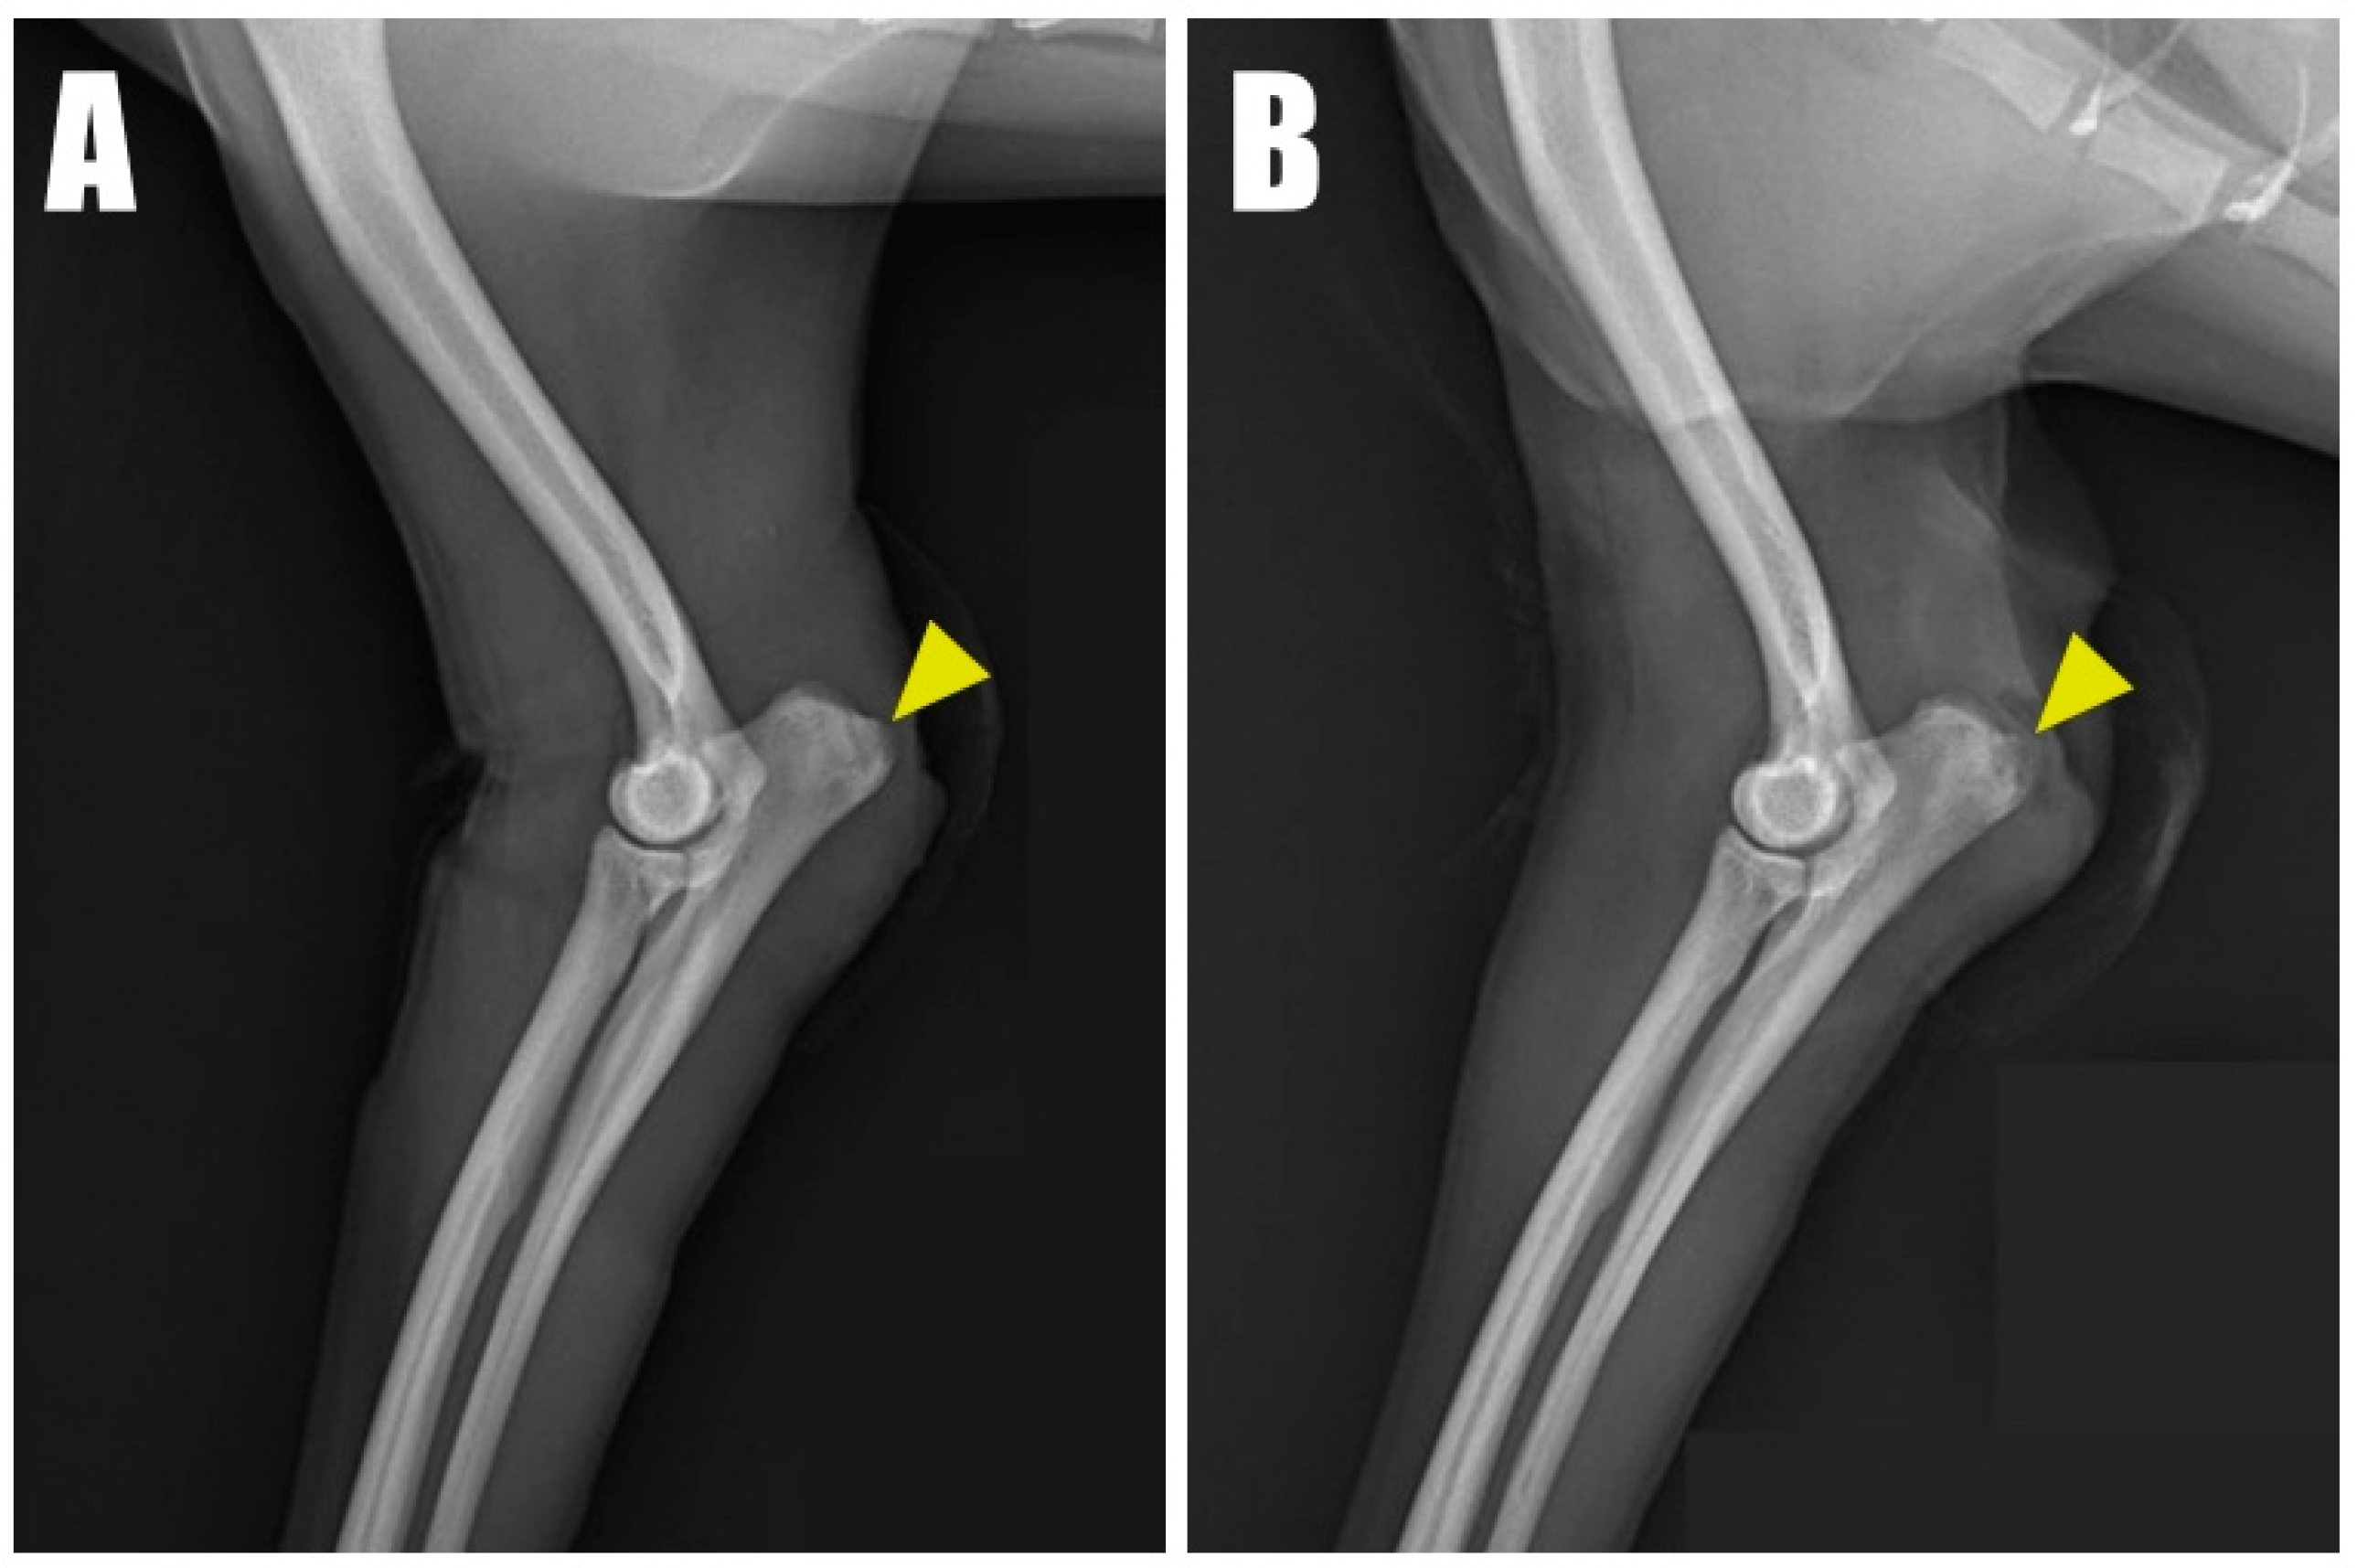

Figure 1B) as follows: four weeks in the left forelimb and three weeks in the right forelimb, each following a fall from a height. Physical examination revealed a pain response and nodular formation in the proximal region of the olecranon, with no extension response during the triceps brachii squeeze test. Radiographs revealed radiolucent opacities on both sides of the olecranon (

Figure 2A,B), and ultrasonography identified defects (

7]. Radiographic evaluations typically identify a flake sign at the triceps brachii tendon attachment, indicative of a potential avulsion injury [

1,